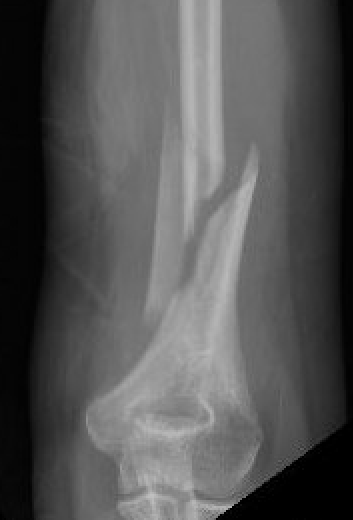

Holstein Lewis / distal humerus fracture